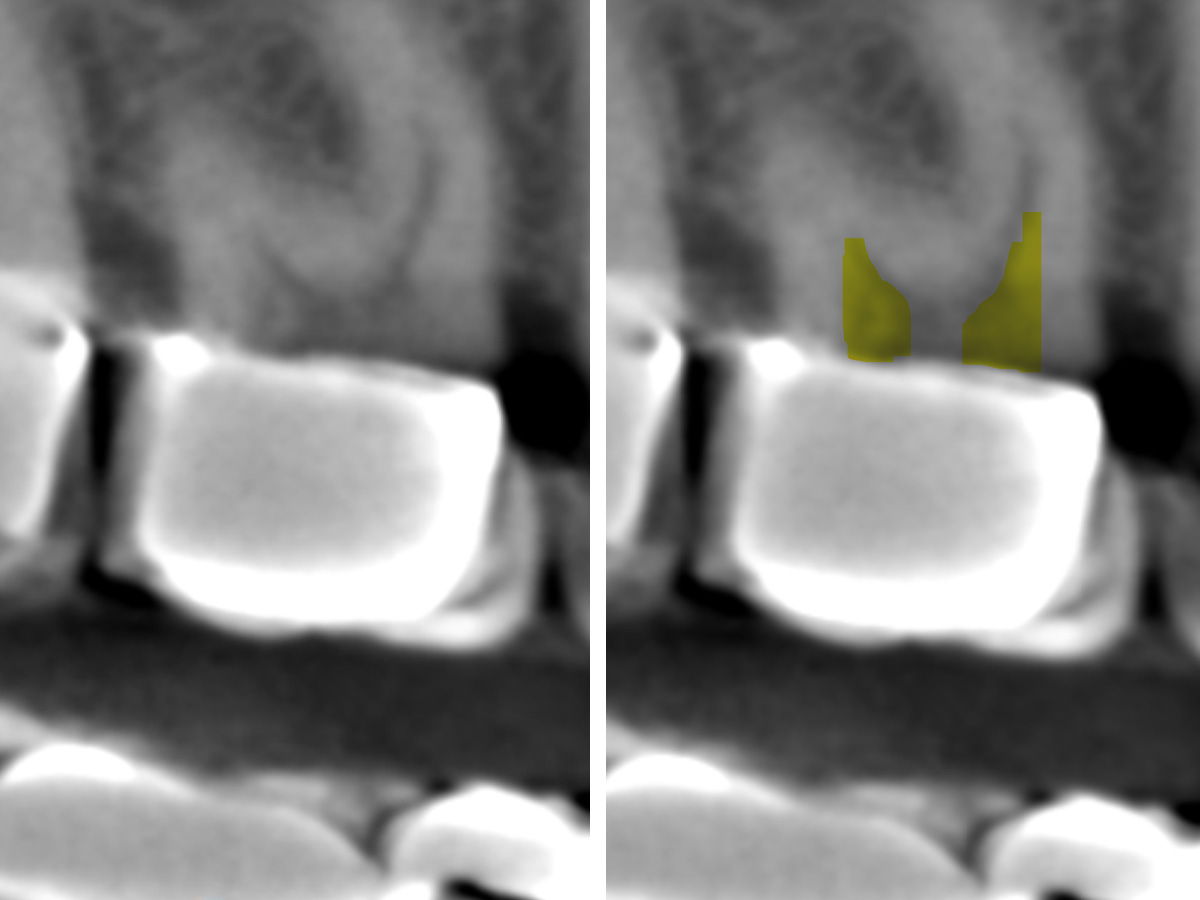

Abbildung 6

Mesiobukkal wurden zwei Kanäle aufbereitet, die apikal in einem Apex konfluieren.

Abbildung 7

Im koronalen Drittel wurden eine schonende Dentinabtragung (grüner Bereich) und Zugang zum Kanal durchgeführt. MB2 (oranger Bereich).